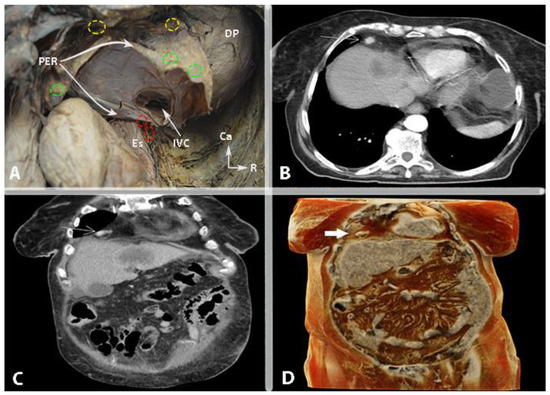

2. Omental Bursa

2.1. Boundaries

2.1.1. Recesses and Vestibule

2.1.2. Hepatoduodenal Ligament and Foramen of Winslow

2.1.3. Vessels

2.1.4. Porta Hepatis

2.1.5. Lymph Nodes

2.2. Omental Bursa and Ovarian Cancer

2.2.1. Transcoelomic Metastases

2.2.2. Omental Bursa Lymph Node Metastases

2.3. Surgical Approaches to the Omental Bursa